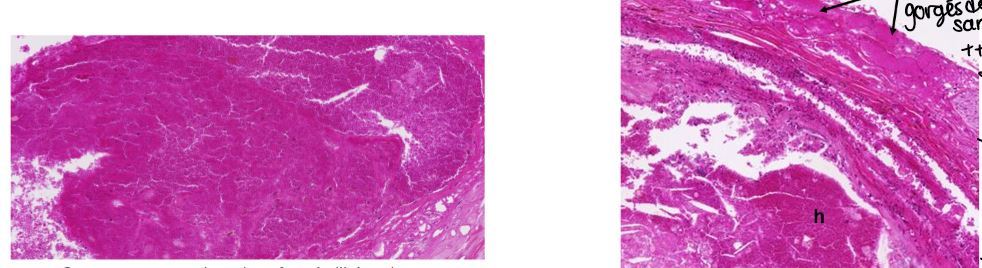

1. thrombus fait d’hématie et plaquettes combinés dans un reseau de fibrine

2. plaque atherosclérotique avec hemorragie dans le coin droit et vasavasorum ++ conjestifs